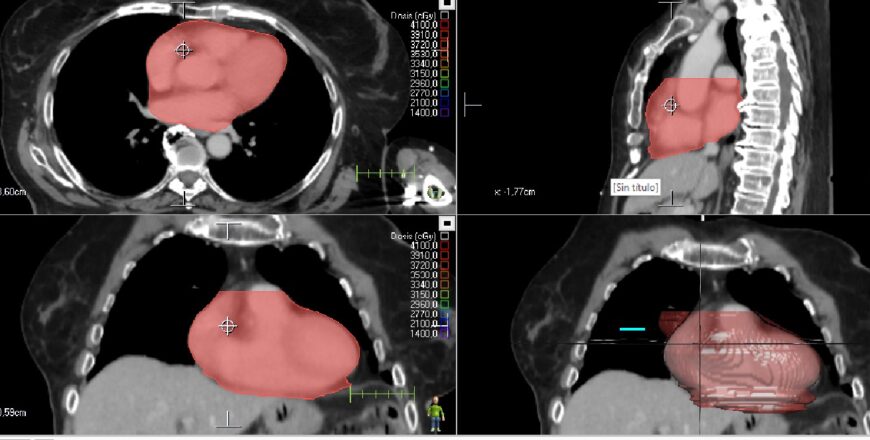

Tórax

caso5_corazón_2